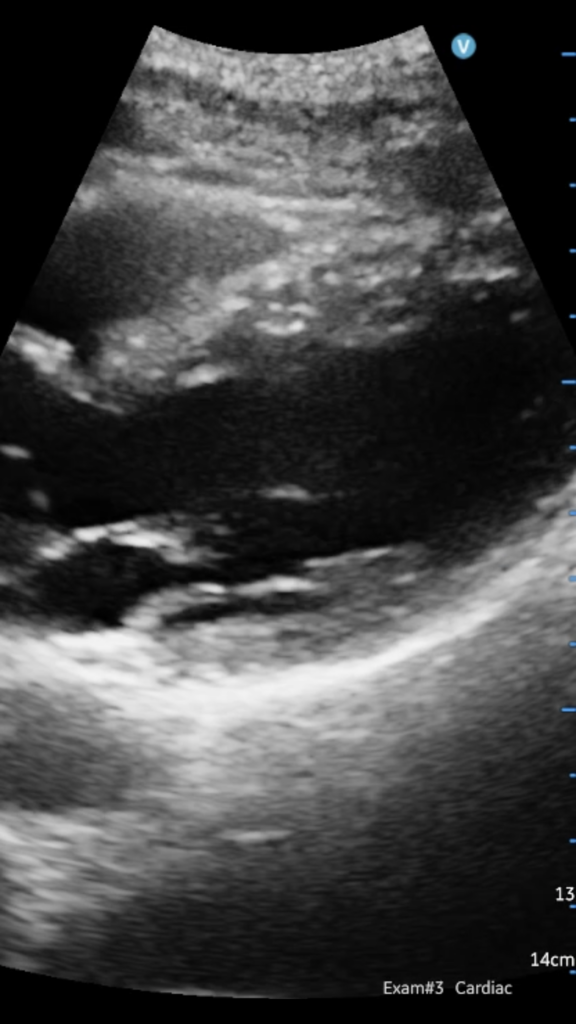

Also, here’s a parasternal long axis view of my heart.

View attachment 345093